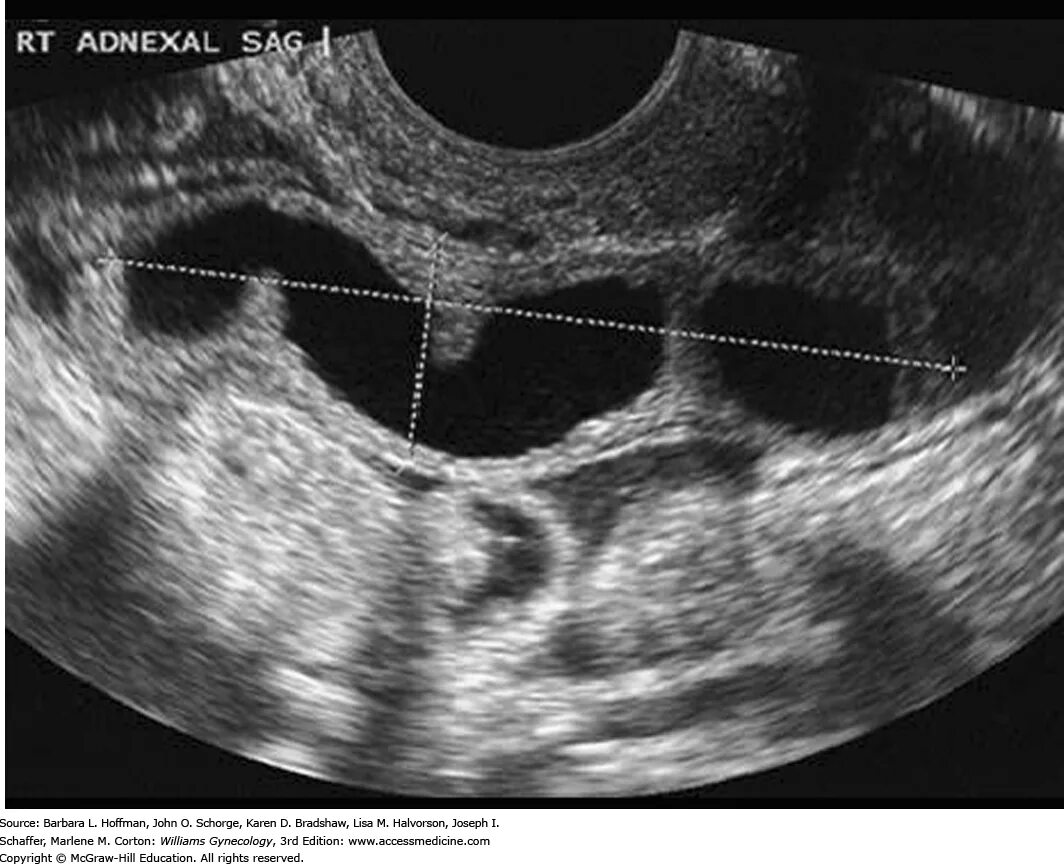

Сальпингит и оофорит что это